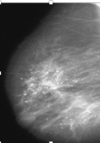

What might mammograpy reveal on breast tissue? [1] What could they be? [2]

**Microcalcifications**: calcium deposits - usually calcium oxalate Could be usual **duct hyperplasia** (benign) OR **neoplastic**